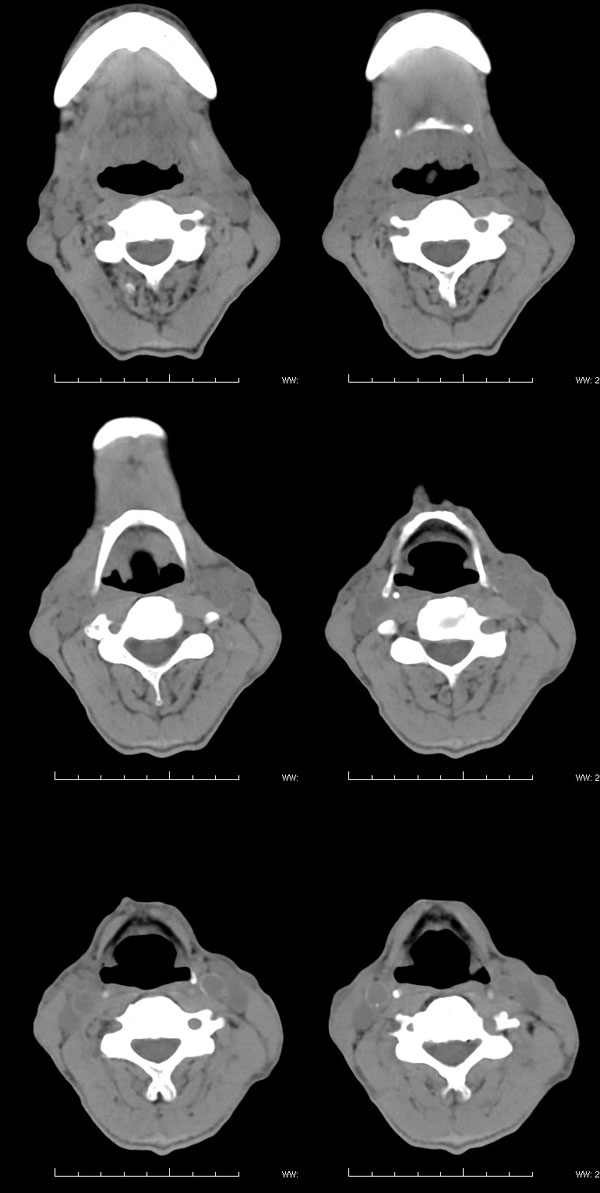

| 男性,57岁。反复声嘶1年,加重半年。 体检:喉粘膜充血,会厌肿胀,上举差,喉室及双声带窥视欠清。              蚂蚁发言:考虑喉癌(声门型)?双侧颈鞘周围淋巴结转移? 徐飞发言:有无呛水?根据病史要考虑球麻痹,脑干应检查 弯三角发言:考虑喉结核,应检查其它部位有无结核 卜一发言:喉腔右侧壁弥漫性软组织增厚,喉腔变窄。支持:喉癌(声门型)!另:双侧颈部多枚淋巴结肿大! 结果: 支纤镜检查:会厌板肿胀,右会厌咽侧壁肿胀,右杓状小结见结节样肿物,喉室肿胀,双声带肿胀、充血,左声带见菜花样肿物,触及易出血,取活检。 病理诊断:高分化鳞状细胞癌。 免疫组化:ck(h)(+++)、pcna(++)、p53(++)、ck(l)(-)。 原贴地址:http://www.radinet.com.cn/forum_view.asp?forum_id=4&view_id=34703 |